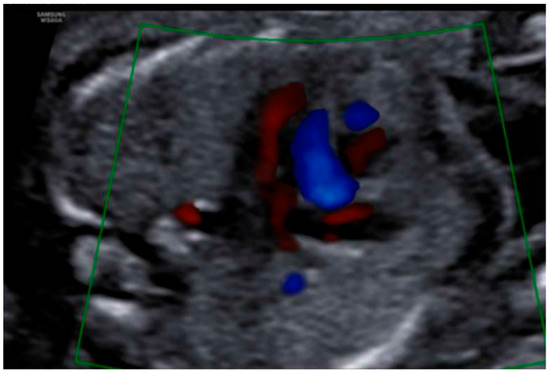

3. Results: Case Presentation